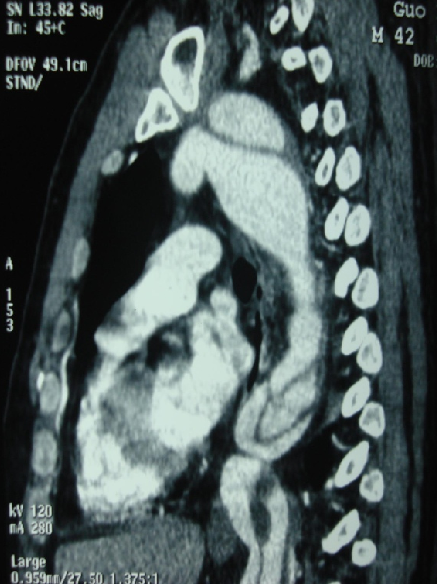

男性,44岁,慢性B型夹层。2010年12月行TEVAR术。

2013年5月发现RTAD,未处理。2015年2月死亡。